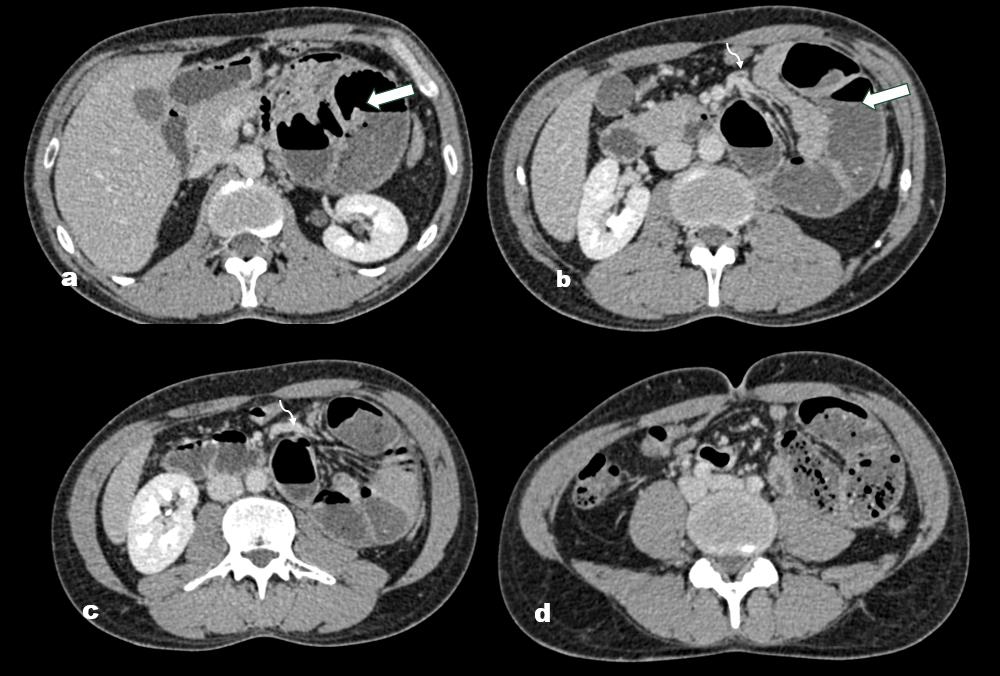

CT (CECT) scan of the abdomen and pelvis was performed

[Figure 2,3].The study demonstrated clustered and dilated jejunal

loops within the left paraduodenal region, contained in a welldefined

hernia sac, with preserved normal bowel wall enhancement

and normal wall thickness. The mesenteric vessels were observed

to converge and traverse through the hernial neck, without signs

of vascular engorgement, thrombosis, or compression. Considering

Figure 2: (a–d): Axial contrast-enhanced CT images of the abdomen

show a cluster of dilated jejunal loops in the left paraduodenal region. The

jejunal loops within the hernia sac appear crowded but maintain normal wall

thickness and enhancement. The mesenteric vessels are seen converging

and passing through the hernia neck. The white arrow indicates the hernia

sac containing jejunal loops, while the curved arrow highlights the mesenteric

vessels near the hernia neck.